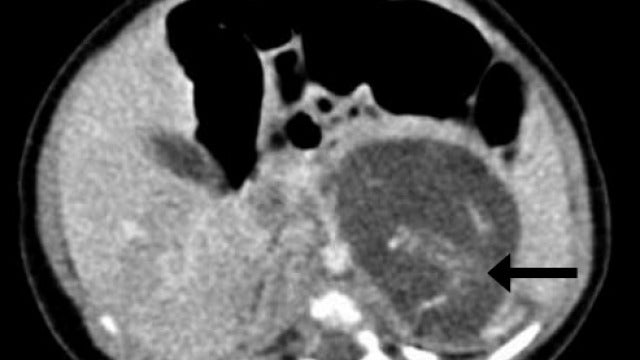

Tomografia computarizada mostrando la espina dorsal de uno de los dos "fetos" Hong Kong Med Journal